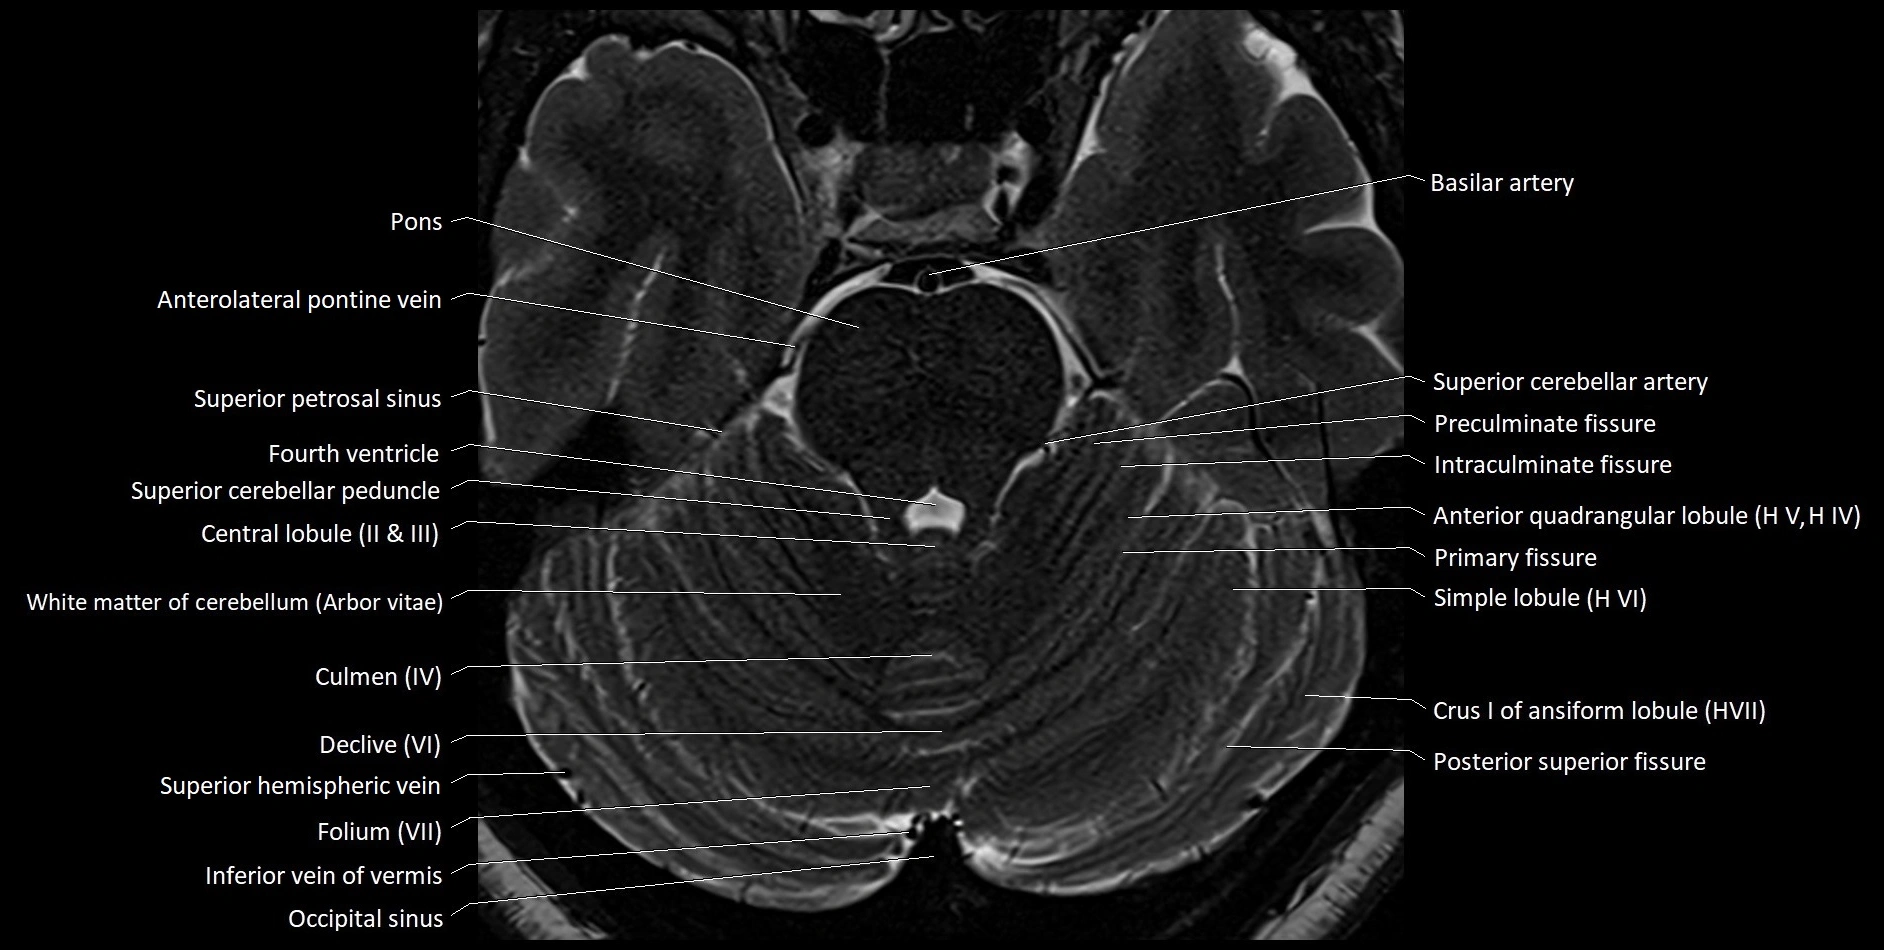

MRI images